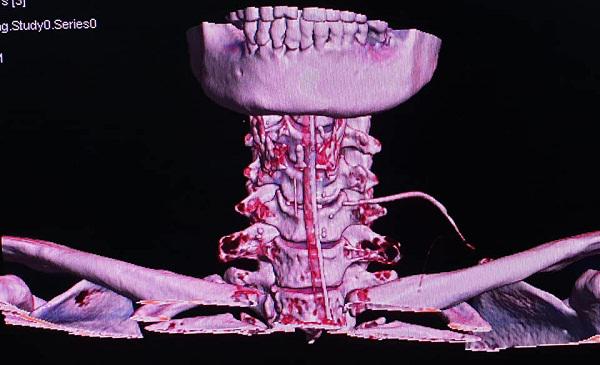

Điển hình như trường hợp của bệnh nhân Nguyễn Thị T. (ở Hải Hậu, Nam Định), nhập viện do bị hóc xương cá. Nguy hiểm hơn, bệnh nhân T. còn bị xương cá đâm xuyên từ thực quản ra ngoài cổ.

BS Thắng cho biết, kết quả chụp phim bệnh nhân cho thấy, bệnh nhân có dị vật (xương cá) đâm xuyên từ lòng thực quản ra vùng cổ, ngay sau đó bệnh nhân được các bác sĩ BV TMH Trung ương mở cạnh cổ lấy dị vật.

Hình ảnh bệnh nhân hóc xương cá và sau khi được lấy ra.

Hình ảnh chụp chiếu phát hiện có dị vật trong thanh quản.